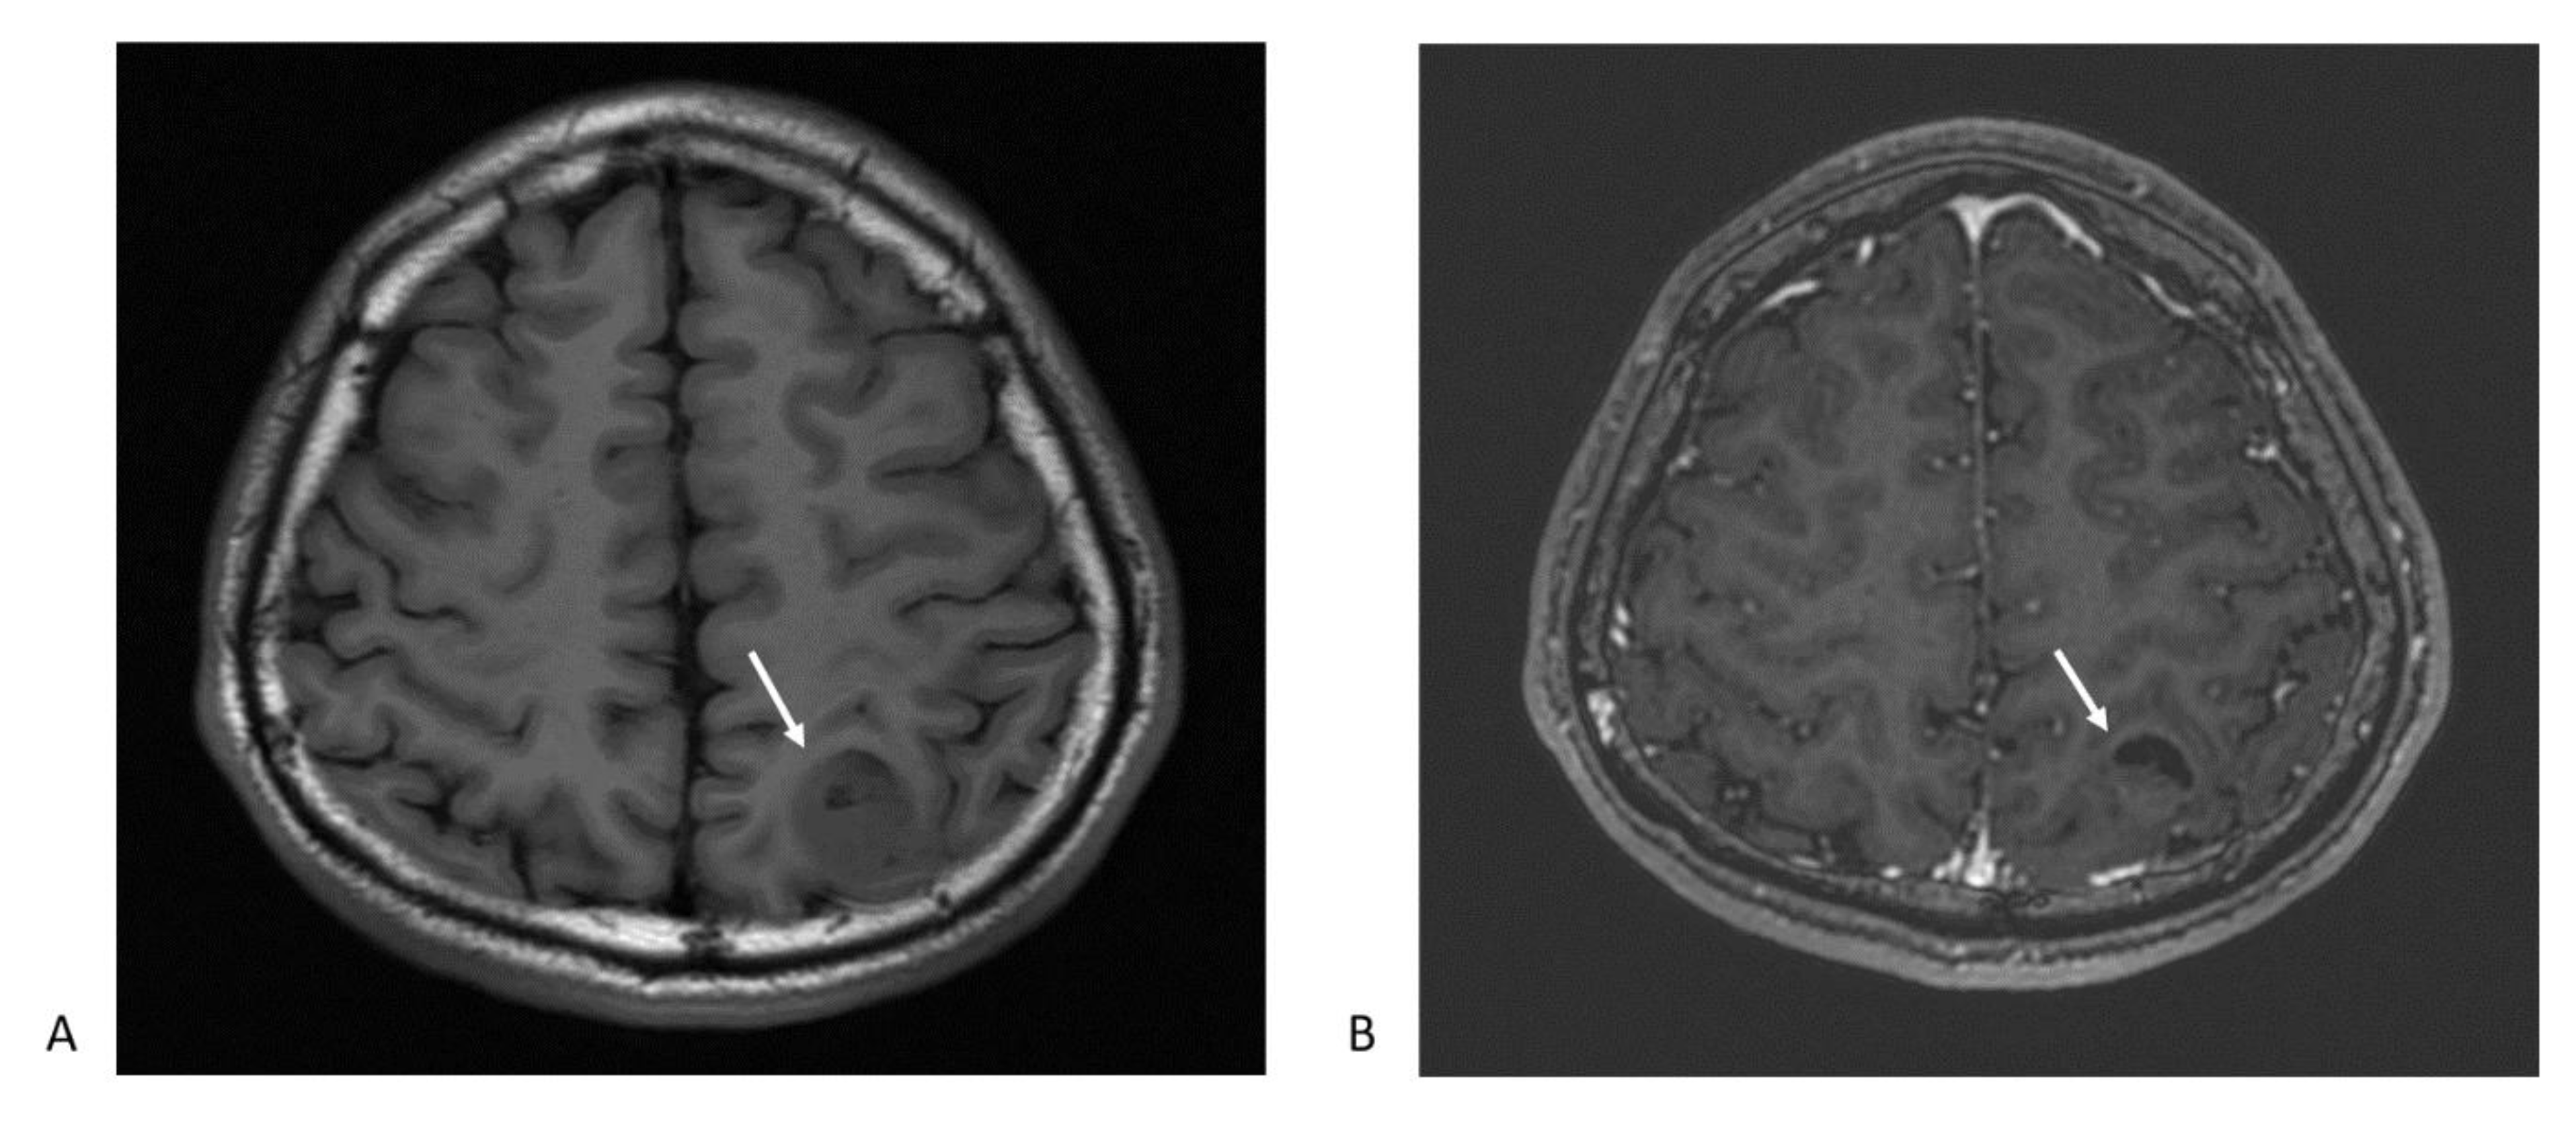

Figure 1.

Magnetic resonance imaging (MRI) typical features glioblastoma multiforme: (A) The axial T1-weighted image shows heterogeneous hypointense mass lesion at left parietal lobe (arrow); (B) postcontrast T1-weighted axial image depicts an enhancing ring lesion with central heterogeneous enhancement. The crescent-shape dark area suggests a necrotic part of the tumor (arrow).